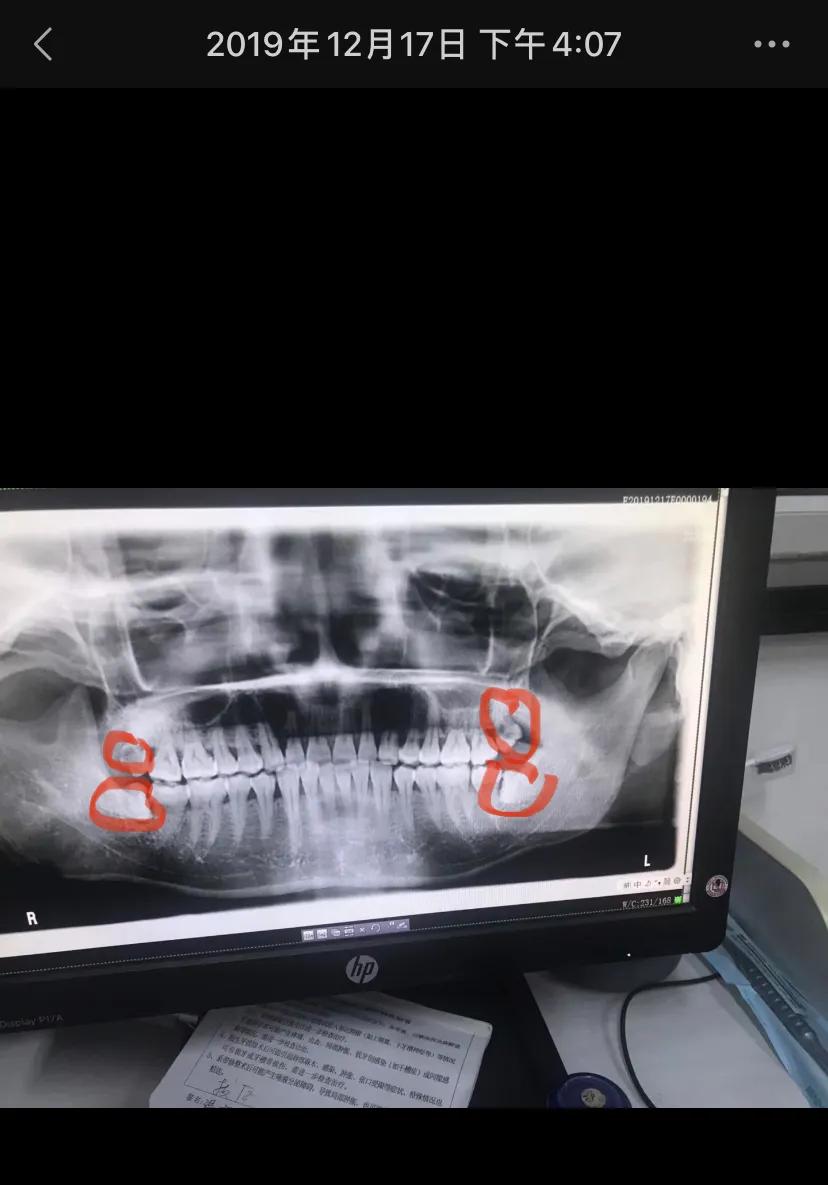

先介绍一下我的四颗智齿,左上和右上是已经长出来的顶着脸皮的2颗,左下和右下是完全埋在肉里横向阻生的智齿,请看第一次检查牙齿拍的图片:

徐汇牙防所-第一颗右上拔除